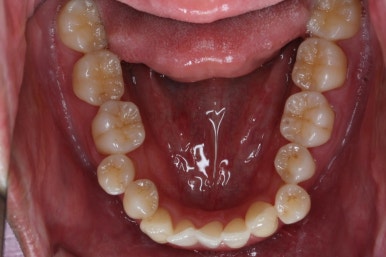

화살표는 사랑니인데요. 이 분의 경우 아래 앞니가 1개 없고, 1개를 추가로 뽑아서 윗니 대비 아랫니가 총 2개 모자란거죠.

운이 좋게도 이 분은 사랑니까지 잘 나와있던 상태라 내버려두기 아까워 함께 가지런하게 해주고 사용하실 수 있게 해드렸어요.

아랫니 갯수가 모자라고 중앙이 맞지 않았고 짝이 안맞는 상황이었으나 비교적 잘 마무리를 했어요.

거꾸로 물리는 상황이 개선되었기 때문에 앞니나 어금니의 교합은 이전과 비교할 수 없을만큼 좋아졌지요.